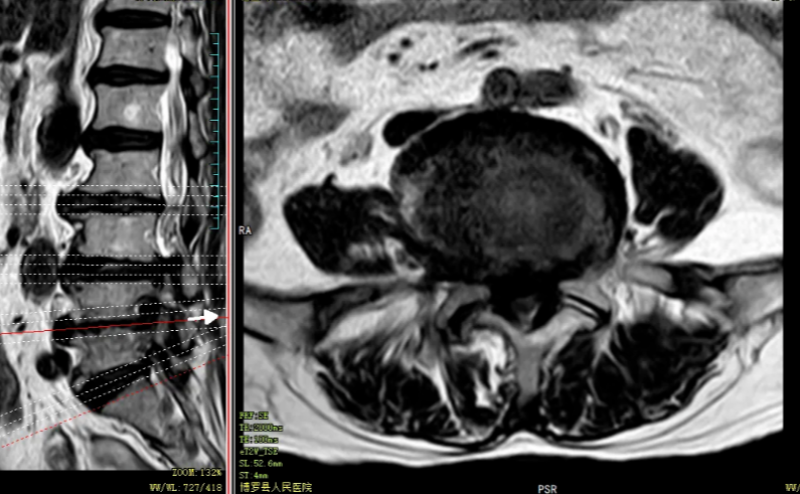

術前MRI:腰3/4、腰4/5椎間盤突出,伴椎管狹窄嚴重、神經根受壓、馬尾神經冗余。